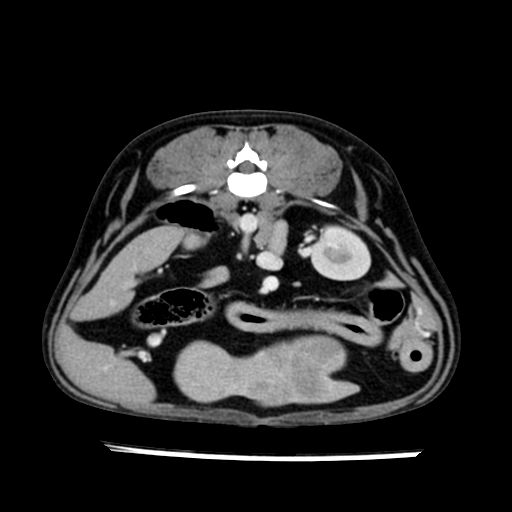

prescritto esame TAC

sequenza immagini limitata al fegato reni e surreni

le immagini ecografiche rispetto alla tac datano circa 7 mesi prima ,le surrenali sono normali nonostante il test acth sia risultato positivo .all’esame TAC dopo diversi mesi risultano aumentate armonicamente nel volume e si individua un forte sospetto di adenoma ipofisario .

sospetto adenoma ipofisario vs. meno probabilmente meningioma della base; intertiziopatia polmonare; lesione espansiva epatica, verosimilmente del lobo laterale sinistro, di sospetta natura neoplastica; lesioni spleniche di natura da definire; iperplasia/ipertrofia delle ghiandole surrenali, bilateralmente; vertebra di transizione del rachide toracico; tenosinovite cronica del muscolo bicipite brachiale di destra.